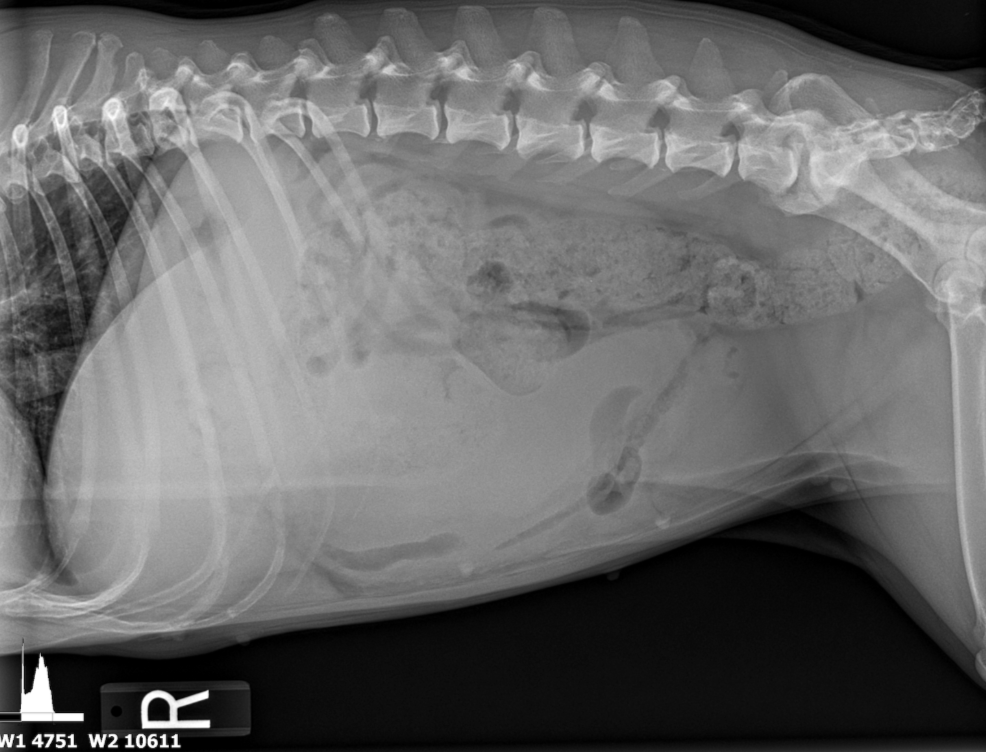

The patient was referred from another veterinary clinic for advanced imaging following the identification of a suspected abdominal mass on radiographs. Ultrasonographic evaluation revealed a splenic mass consistent with an abscess, from which purulent fluid was aspirated and drained. A splenectomy was scheduled for later the same day.

The spleen revealed an expansive parenchymal mass that measured 10+ cm without evidence of cavitation. Hyperechoic fat was noted around the spleen. This is consistent with inflammation.

- Splenic mass.

There was no obvious evidence of metastatic disease. Proactive splenectomy, liver inspection and biopsy was indicated. Rapid echocardiogram was recommended if not already performed to ensure that metastatic disease was not present. Differentials included benign hyperplasia, hemangiosarcoma and round cell neoplasia. However, the mass was highly precarious and at risk for rupture.